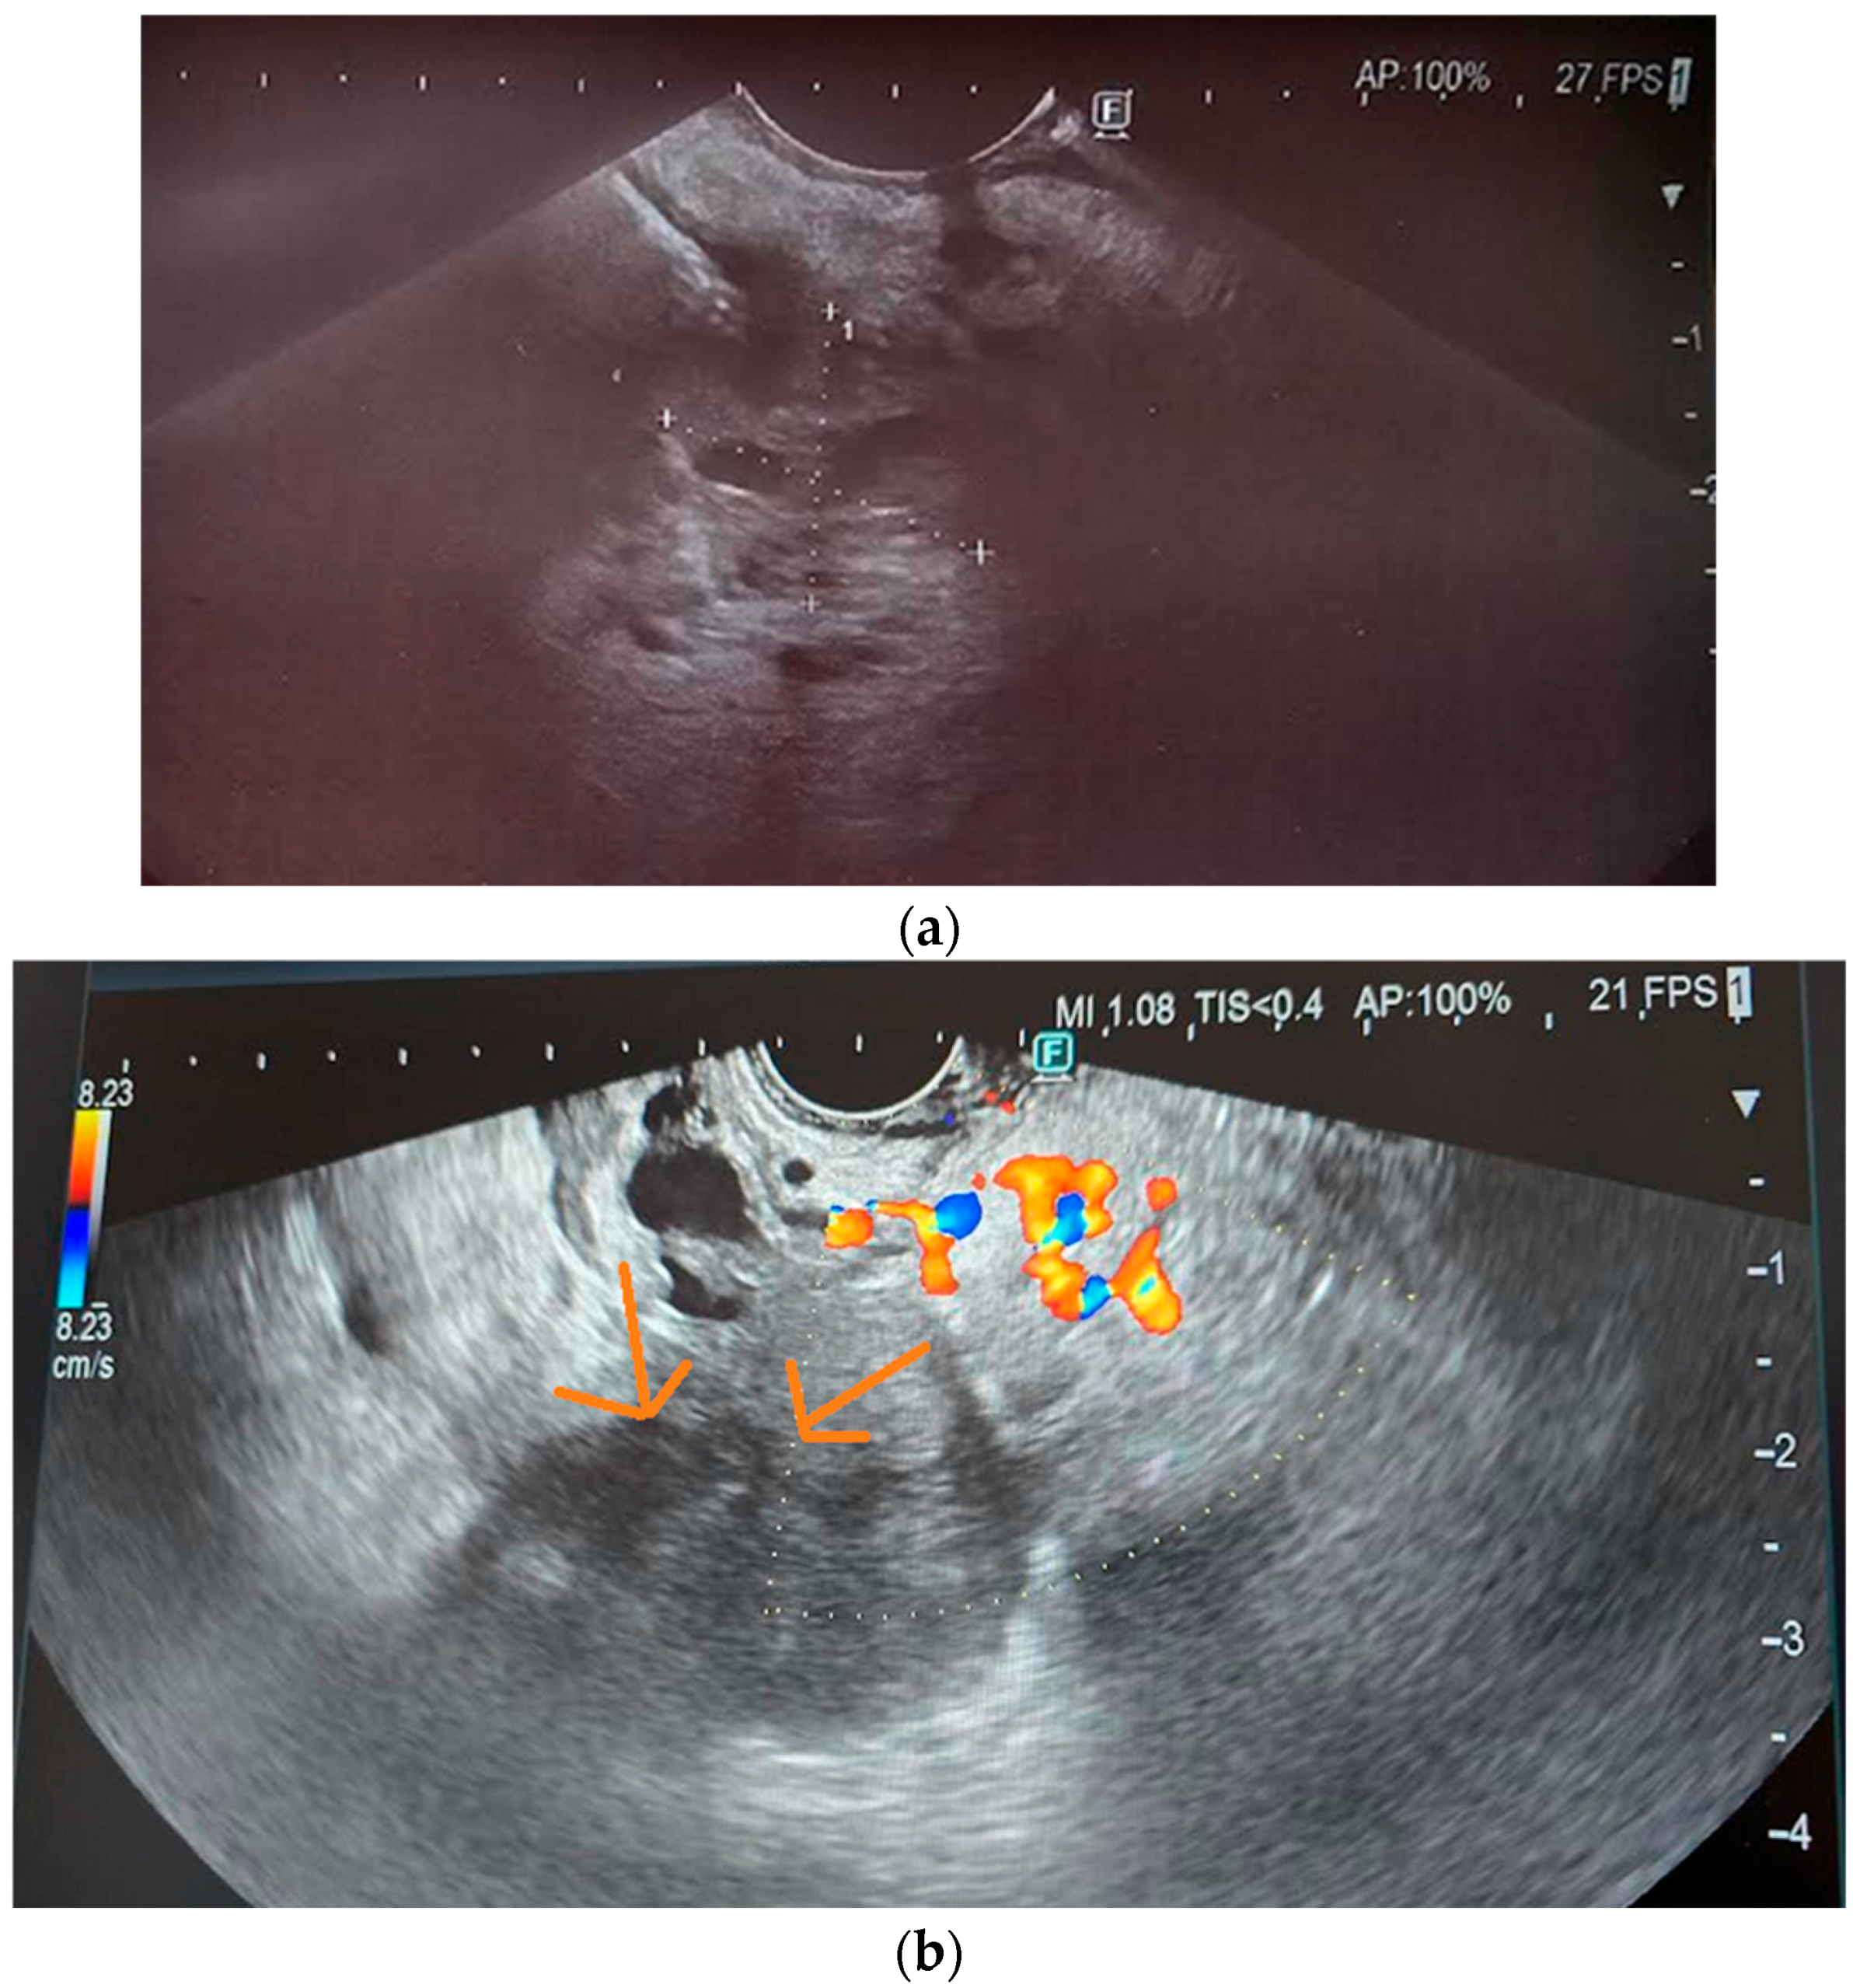

3.5. Endoscopic Ultrasound

10.4. Endoscopic Ultrasound

11.4. Contrast-Enhanced EUS (CE-EUS)